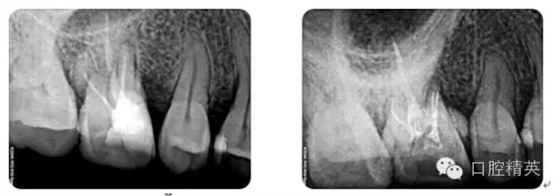

病例6:折斷器械取出

病例7:根尖切除術